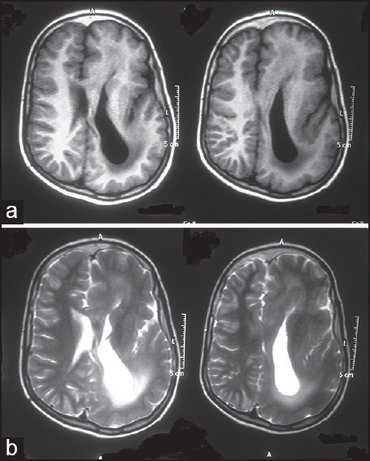

Linear nevus sebaceous syndrome-(a)Left hemimegalencephaly with agyria-pachygyria complex b)left ventricle colpocephaly

The major neurological abnormalities include mental retardation to varying extent, seizures, and hemiparesis.[7] Seizures, when present, typically begin during the first year of life.[8] The most common structural central nervous system abnormalities in Schimmelpenning syndrome are hemimegalencephaly and ipselateral gyral malformations.[3]